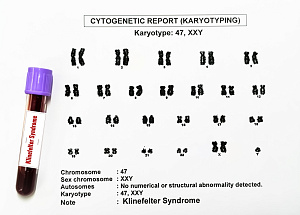

Метаболический профиль пациентов с синдромом Клайнфельтера